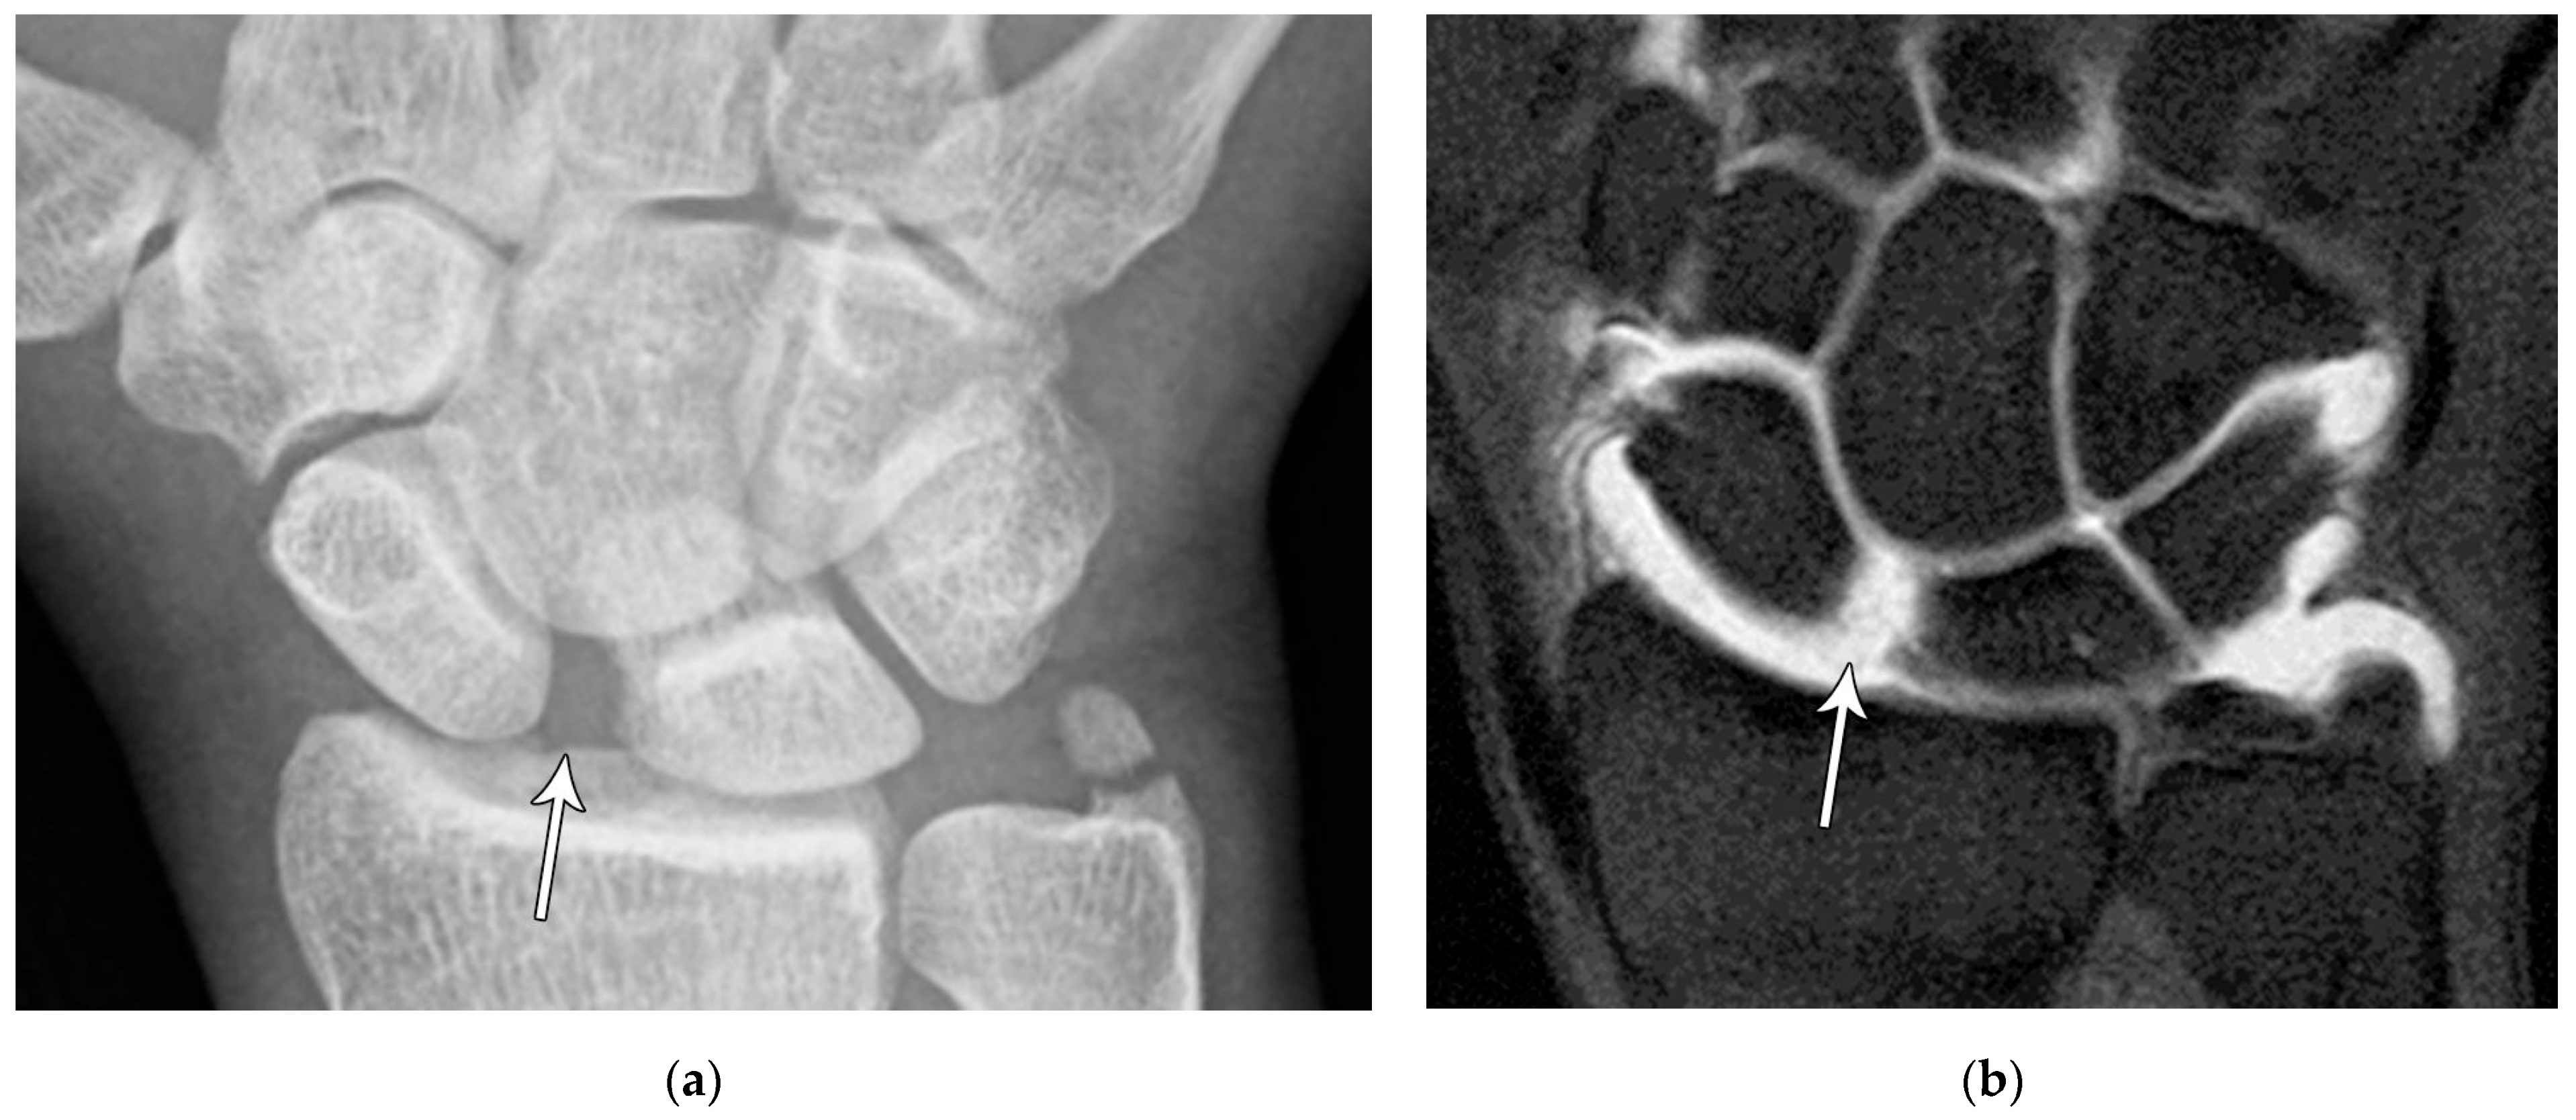

Common scaphoid fracture complications include avascular necrosis and nonunion [10]. Avascular necrosis is a dreaded outcome resulting from the loss of the proximal arterial supply due to the distal entry point of nutrient vessels. This retrograde perfusion of the proximal pole makes it vulnerable to losing its vascular supply when fractured. Sclerosis of the proximal pole indicates osteonecrosis (Figure 5). With scaphoid nonunion, biomechanical alterations contribute to rapidly progressive degenerative arthritis and instability referred to as scaphoid nonunion advanced collapse (SNAC) [16]. Nonunion occurs in 5–10% of cases and has a higher incidence in displaced fractures (Figure 6). During wrist extension, the distal scaphoid fragment rotates into flexion while the proximal scaphoid fragment extends with the lunate. The resultant abnormal contact between the distal fragment and radius begins the first stage of degenerative collapse. This progresses into the second stage as scaphocapitate osteoarthritis develops and finally to the third stage with progression to capitolunate osteoarthritis and proximal radial migration of the capitate dorsal to the lunate. Treatment of SNAC wrists, depending on the degree and severity of the osteoarthritic collapse, includes scaphoidectomy with four-corner arthrodesis or wrist fusion [17]. Four-corner fusion helps reduce joint pain while maintaining some range of motion, as opposed to total wrist fusion (Figure 7). Another option is proximal row carpectomy with resurfacing capitate pyrocarbon implant placement [18].

Figure 5. (a) PA radiograph showing marked sclerosis (arrow) of the proximal pole of the scaphoid after a scaphoid fracture. (b) Coronal reformatted CT in a different patient showing sclerosis (arrow) of the proximal pole of the scaphoid after a scaphoid fracture, indicating osteonecrosis.